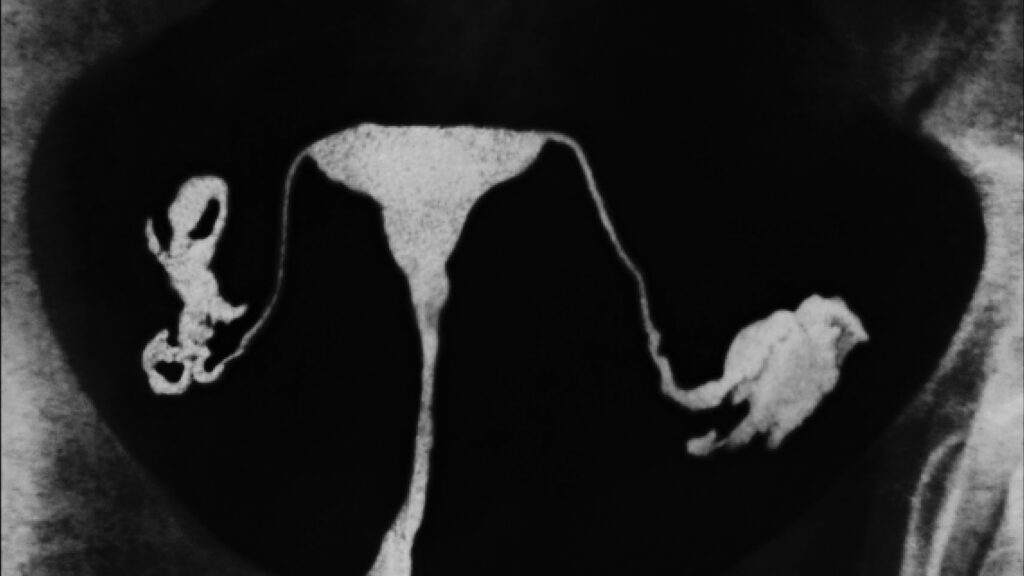

A woman shares her experience of having her fallopian tubes removed to reduce her risk of ovarian cancer, highlighting recent research showing that prophylactic salpingectomy can cut ovarian cancer risk by up to 80%. Despite strong evidence and endorsements from medical organizations, awareness and adoption of this preventive surgery remain limited due to systemic barriers and lack of public education. Experts advocate for increased awareness and integration of salpingectomy into routine medical procedures for women at risk or undergoing abdominal surgeries.